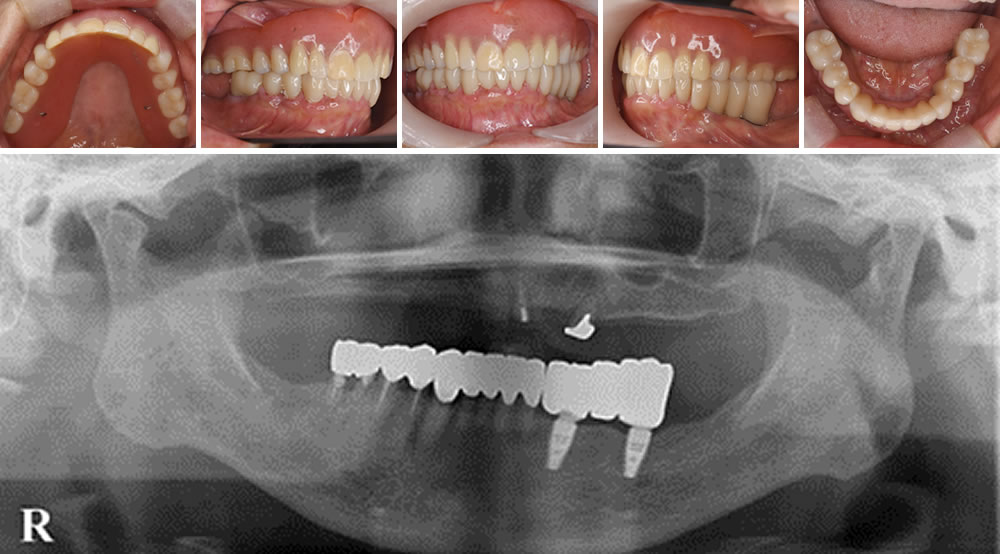

インプラントと入れ歯で咬み合わせを回復した症例

前歯が腫れて痛いとの主訴で来院された60代女性の患者さまです。

患者さまと相談し、動揺の激しい上顎の歯は抜歯して保険の入れ歯へ、下顎は左下2本をインプラントにして残存歯はセラミックで治療することになりました。

治療完了

計画通り、上顎は保険の入れ歯、下顎はインプラントとセラミックで咬み合わせを回復しました。見た目もきれいになり、患者さまも喜んでおられました。

| 年齢・性別 | 60代 女性 |

|---|---|

| 治療期間 | 6ヵ月 |

| 治療回数 | 23回 |

| 治療費 | 2,000,000円(税込) |

| リスク・注意点 | ・セラミックは部分的に強い力がかかると、まれに割れることがある ・インプラントは歯周病になる可能性ある |